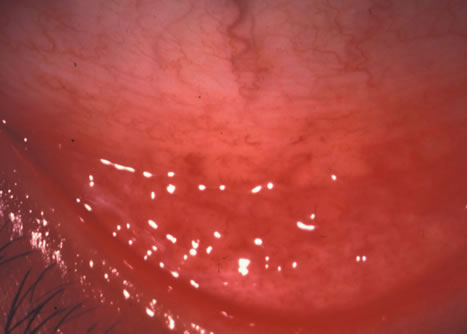

Clinically, follicles are yellowish to grayish white, discrete, round elevations of the conjunctiva. The central part of the follicle is avascular, but dilated blood vessels may surround the base and sweep up from the base over the convexity (Figs. 1 and 2). Follicles are 0.2 to 2 mm in size, although larger follicles may be seen, particularly in chlamydial disease.3

Fig. 1. Nonspecific follicular conjunctivitis demonstrating the classical appearance of follicles in the inferior fornix. (Courtesy of Peter R. Laibson, MD.)